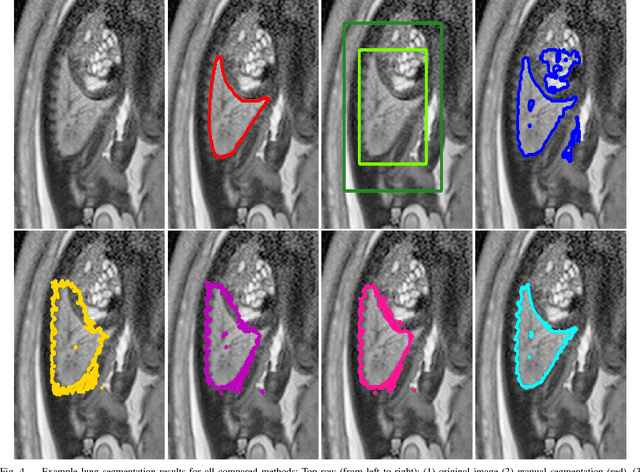

Abstract:In this paper, we propose DeepCut, a method to obtain pixelwise object segmentations given an image dataset labelled with bounding box annotations. It extends the approach of the well-known GrabCut method to include machine learning by training a neural network classifier from bounding box annotations. We formulate the problem as an energy minimisation problem over a densely-connected conditional random field and iteratively update the training targets to obtain pixelwise object segmentations. Additionally, we propose variants of the DeepCut method and compare those to a naive approach to CNN training under weak supervision. We test its applicability to solve brain and lung segmentation problems on a challenging fetal magnetic resonance dataset and obtain encouraging results in terms of accuracy.

Abstract:The availability of training data for supervision is a frequently encountered bottleneck of medical image analysis methods. While typically established by a clinical expert rater, the increase in acquired imaging data renders traditional pixel-wise segmentations less feasible. In this paper, we examine the use of a crowdsourcing platform for the distribution of super-pixel weak annotation tasks and collect such annotations from a crowd of non-expert raters. The crowd annotations are subsequently used for training a fully convolutional neural network to address the problem of fetal brain segmentation in T2-weighted MR images. Using this approach we report encouraging results compared to highly targeted, fully supervised methods and potentially address a frequent problem impeding image analysis research.